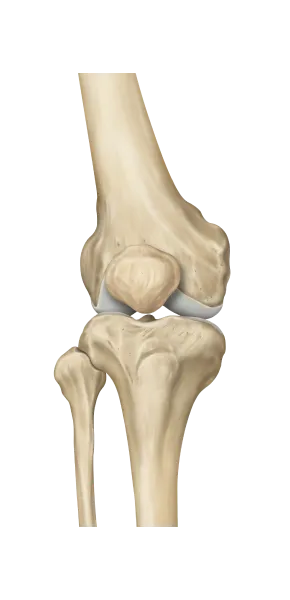

무릎

무릎의 변형을 발질환에 많은 영향을 미칩니다.

O 다리나 X 다리 , 무릎이 뒤로 밀려난 슬관절과신전 패턴 등은 보행패턴을 망가뜨리고 정상적인 보행을 방해하여 발질환을 만성화시키는 주 원인이 됩니다.